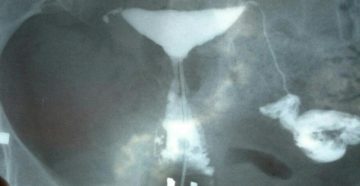

Непроходимость маточных труб, можно ли забеременеть: отзывыThis is an example title — edit by clicking…